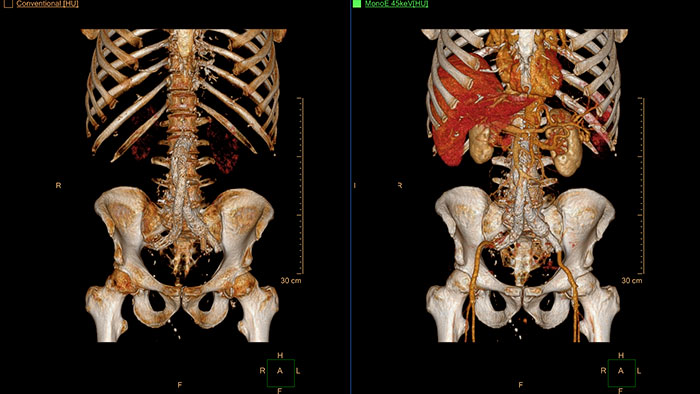

Streamlined modeling workflow

Allows to view volumetric images of anatomical structures, perform segmentation, edit and combine segmented elements (tissues) into a 3D model.

Streamlined workflow for follow up and analysis of oncology patients

MMTT is a post processing software used to display, process, analyze and quantify anatomical and functional images, for CT, MR, PET/CT, SPECT/CT and Dual Energy CT at one or multiple time points.